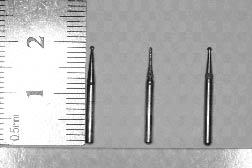

Принцип микропрепарирования в терапевтической стоматологии заключается в максимальном сохранении тканей зуба за счет удаления только тех кариозных участков, которые не могут быть вылечены. Для минимизации объема препарированных тканей в Клинике «Ортокон плюс» используются боры сверхмалых размеров, позволяющие точечно убирать некротизированные участки эмали и дентина.